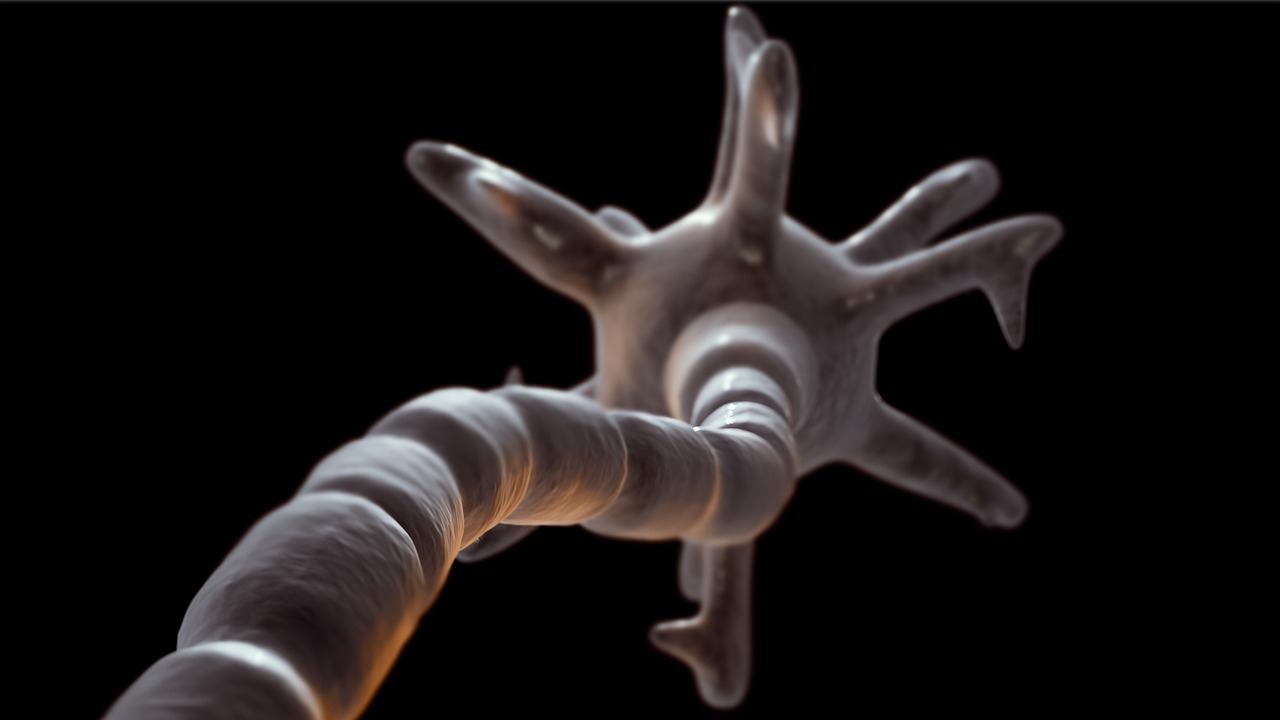

MSは、免疫システムが神経の「ミエリン鞘(myelin sheath)」という脂肪の保護層を誤って攻撃することにより発症します。

このミエリン鞘が破壊されると、脳と身体の間の情報伝達が遮断され、運動障害や感覚麻痺、さらには視力障害や記憶力・集中力の低下といった認知機能障害が発生するのです。

すでにこの段階で神経が損傷を受けている可能性が高いことを、今回の研究は示唆しています。